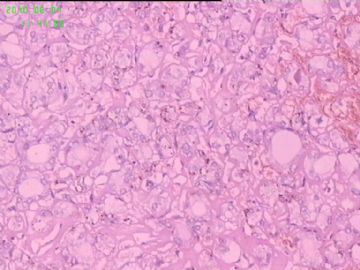

灰白结节2枚,其一2.5x1.8x1.5cm,包膜完整,内为褐色胶质,其二3x2.5x1.5cm包膜完整,切面灰白实性。附件镜下为后者。

可能楼主看到那些核的变化吧?但是没有其他支持的条件,还是应该是结甲。

就这几幅图似乎不够说明问题,细胞有一定的异型性,但是,最好能采到交界处的情况再判断。癌与非癌,最好能有组织结构与细胞异型性结合来看。

有些核透明,无其它特点,恶性证据是没有。

要看肿瘤包膜情况。